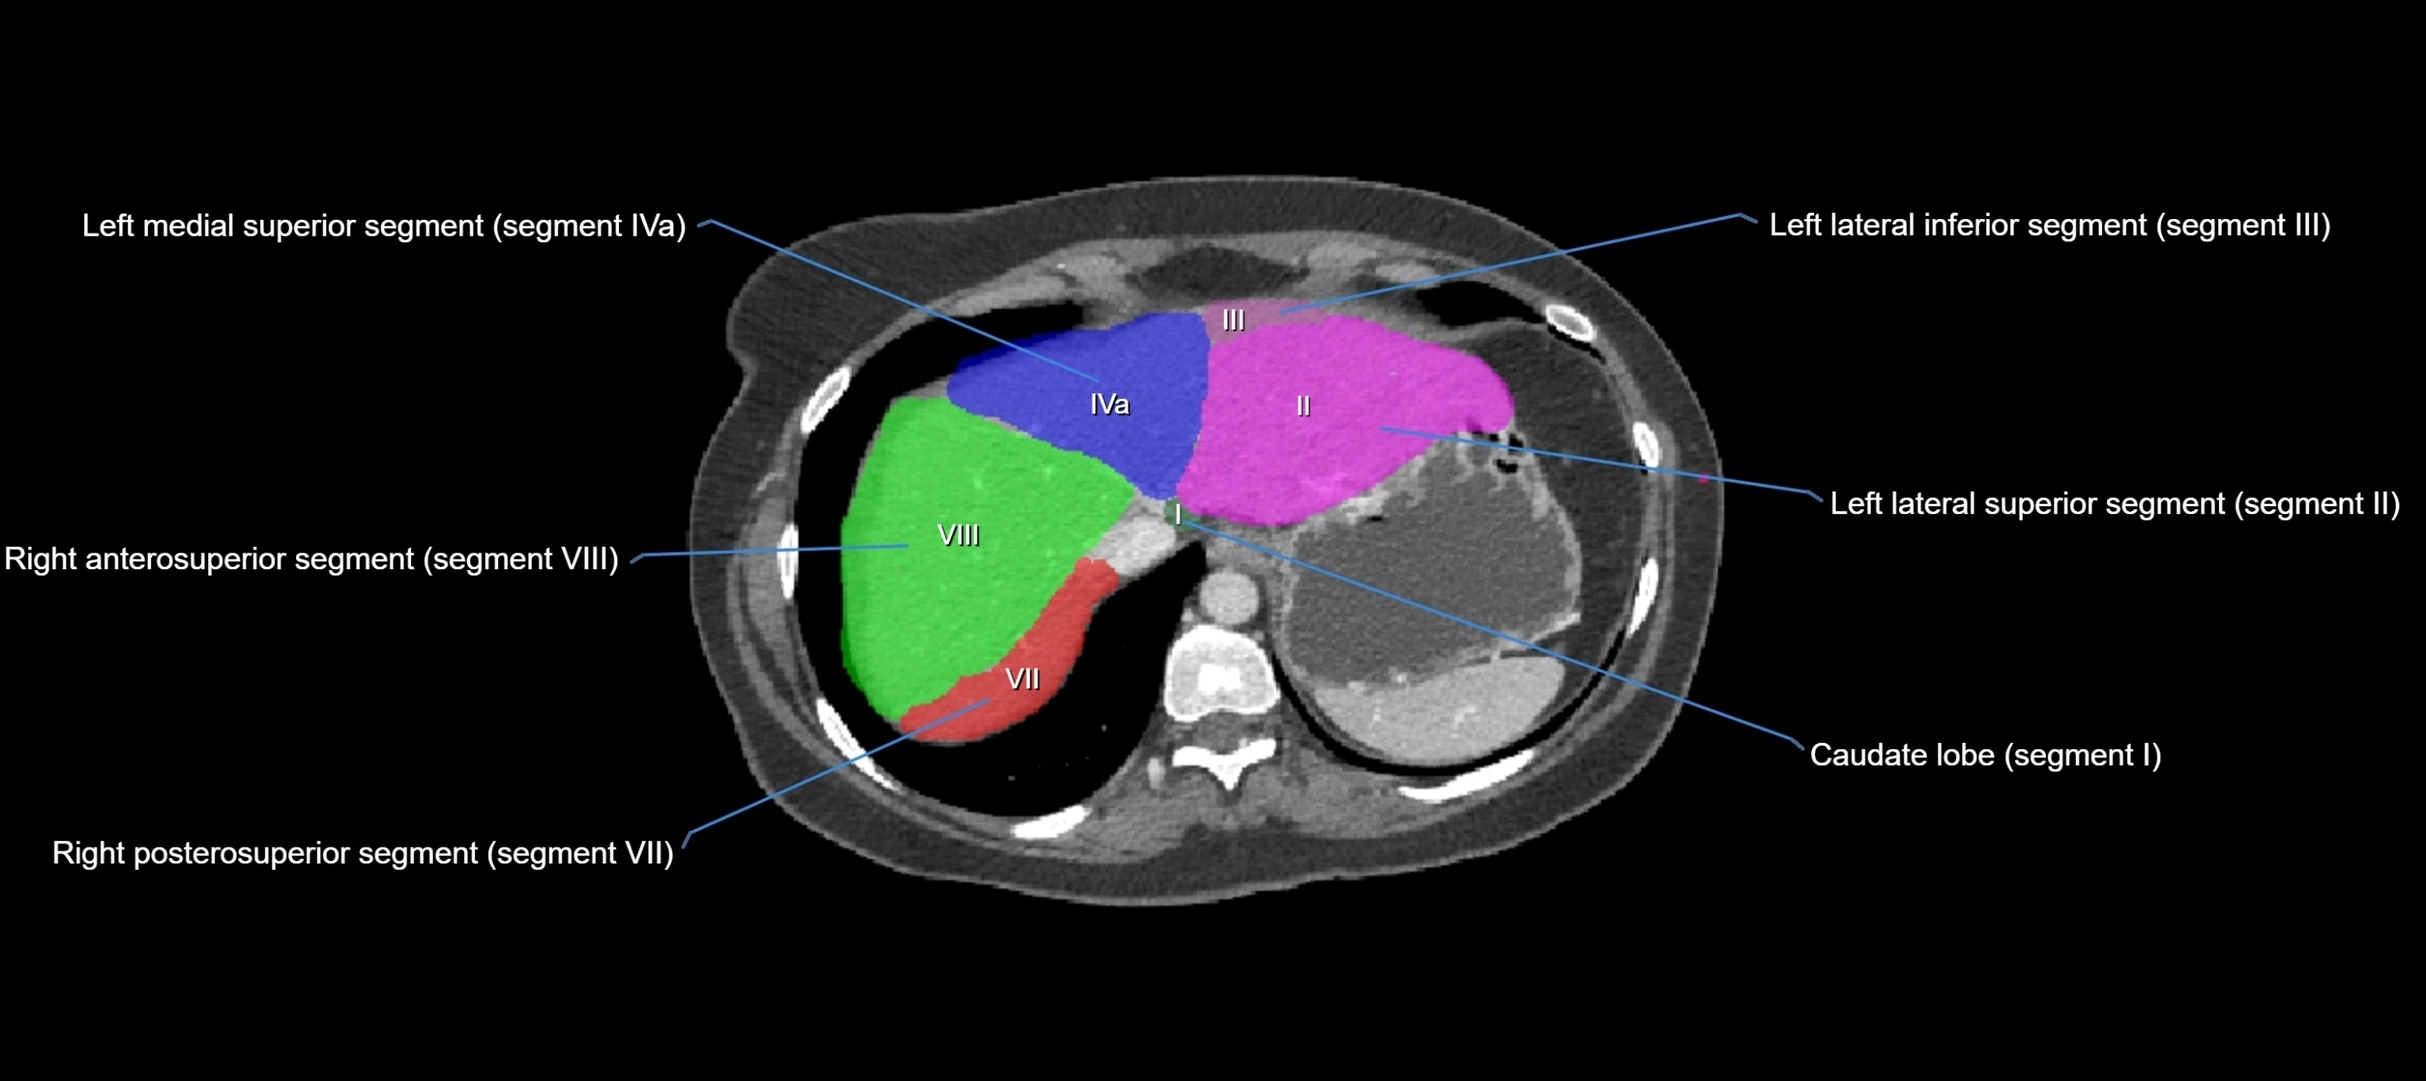

Caudate lobe of liver

The caudate lobe of the liver is a distinct anatomical subdivision of the liver, designated as segment I in Couinaud’s classification. It lies on the posterior surface of the liver, between the fissure for the ligamentum venosum (left boundary) and the groove for the inferior vena cava (IVC) (right boundary). Superiorly, it is related to the posterior liver surface, and inferiorly it is separated from the left lobe by the porta hepatis.

The caudate lobe is unique because it receives dual portal venous and arterial inflow from both the right and left portal veins and hepatic arteries. It also has independent venous drainage directly into the IVC via multiple small hepatic veins, unlike other lobes that drain through the three main hepatic veins.

This anatomical autonomy makes the caudate lobe especially significant in liver surgery, transplantation, and hepatic venous outflow obstruction syndromes (e.g., Budd–Chiari syndrome). Enlargement of the caudate lobe is a characteristic imaging feature in chronic liver disease and cirrhosis.

CT Appearance

CT Pre-Contrast:

• Caudate lobe appears as a soft-tissue density, isodense to the rest of the liver

• Enlargement may be appreciated in cirrhosis or Budd–Chiari syndrome

CT Post-Contrast:

• Homogeneous enhancement in the portal venous phase, similar to rest of liver

• Independent venous drainage into the IVC may be visualized

• Lesions follow characteristic CT enhancement patterns (HCC: arterial hyperenhancement with washout; hemangiomas: peripheral nodular enhancement with centripetal fill-in)

CT Venous Phase (functional significance):

• Caudate lobe often enhances relatively more than other lobes in Budd–Chiari syndrome, due to preserved venous outflow

CT Image

image